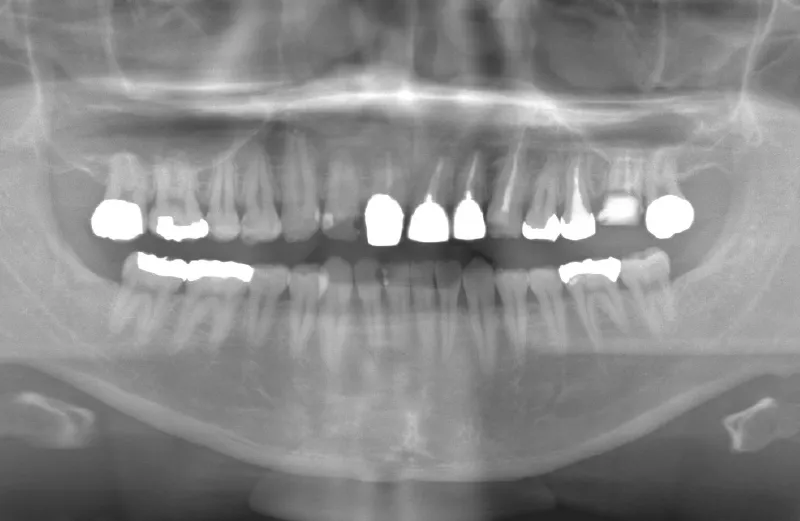

メガジェンオペの症例紹介01

治療前

治療後

| 主訴 | 入れ歯は以前に入れたことがあるが違和感が強く入れられなかったので右上左上をインプラントで治療して欲しい。 左上は他院では上顎洞までの垂直骨量が1mm程度しかないのでサイナスリフトが必須であり、インプラント治療で歯が入るまでに1年以上かかると言われたのでセカンドオピニオンを希望で来院。 |

|---|---|

| 治療期間 | 右上は2.5ヶ月、左上は3.5ヶ月で仮歯が入り、 4.5ヶ月で最終補綴物が入って終了。 |

| 治療費 | 約2,300,000円 |

| 治療内容 | エクストラワイドショートインプラントを埋入し、上顎洞を移植材を用いずに挙上しインプラントを埋入した。仮歯を装着し、様々な機能面に問題がないことを確認し4.5ヶ月で最終補綴物を装着して終了した。 |

| 治療の リスク |

インプラント埋入オペ時に術者が上顎洞内にインプラントを迷入させる可能性がある。これは術者が技術的に熟練していれば防ぐことが可能。 |